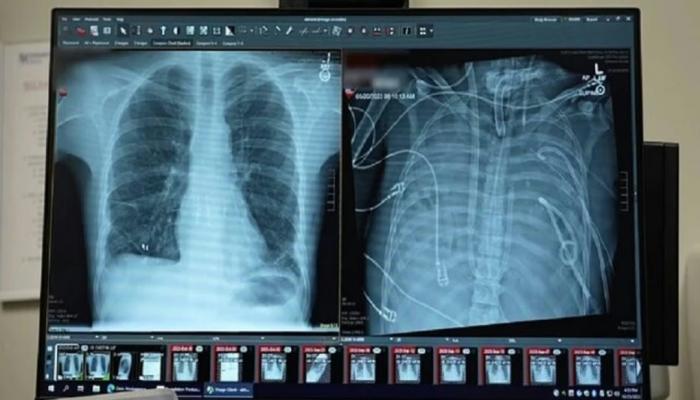

پزشکان از یک دستاورد کمسابقه در علم پزشکی خبر دادهاند که طی آن مردی ۳۳ ساله توانست به مدت ۴۸ ساعت بدون ریههای خود زنده بماند.

این بیمار که به دلیل ابتلا به ویروس آنفلوآنزا دچار سندرم حاد دیسترس تنفسی شده بود، در شرایطی قرار گرفت که ریههایش دیگر قادر به جذب اکسیژن کافی نبودند. با وخیمتر شدن وضعیت، او به دستگاه ونتیلاتور متصل شد، اما بهدنبال عفونتی مقاوم به دارو، بخشهایی از ریههایش پر از چرک شد و بیمار وارد شوک سپتیک شد؛ مرحلهای که در آن قلب و کلیهها نیز شروع به از کار افتادن کردند.

انکیت بهارات، جراح قفسه سینه و عضو دانشکده پزشکی فاینبرگ دانشگاه نورثوسترن، توضیح میدهد که بیمار در آستانه مرگ قرار داشت و حتی دچار ایست قلبی شده بود. از آنجا که وضعیت جسمانی او اجازه پیوند فوری ریه را نمیداد، تیم پزشکی تصمیم گرفت ریهها را که منبع اصلی عفونت بودند، بهطور کامل خارج کند و بیمار را به یک سیستم ریه مصنوعی متصل نگه دارد؛ سیستمی که جریان خون طبیعی و پیوسته به قلب را حفظ میکند.